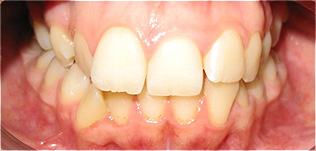

Apinhamento dentário com os dentes caninos em desoclusão (classe II, divisão 2).

![]() |

Após dois anos de tratamento ortodôntico.